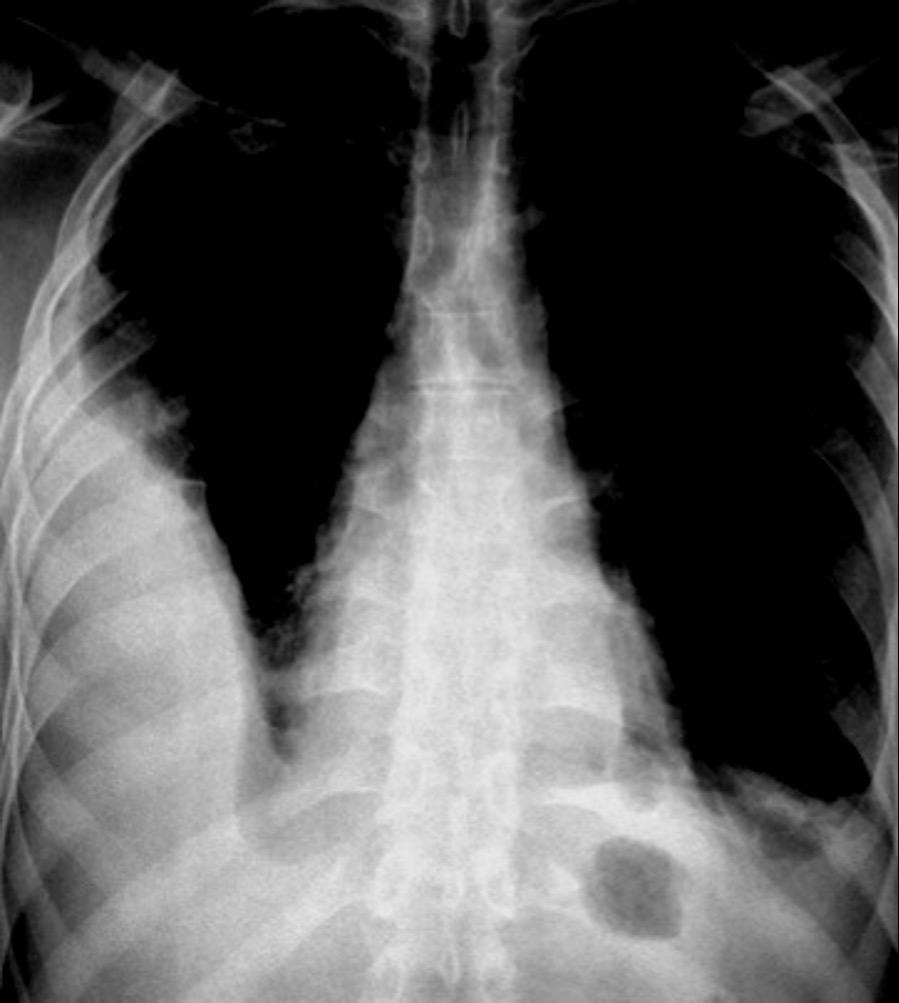

85. ENSANCHAMIENTO MEDIASTÍNICO AGUDO

117. MASA MEDIASTÍNICA DE DENSIDAD AGUA

Rotura de aneurisma aórtico

Mediastinitis aguda

Absceso mediastínico

TRAUMA

Rotura esternal

Hematoma mediastínico

Rotura aórtica

Fractura vertebral

Rotura esofágica Perforación esofágica